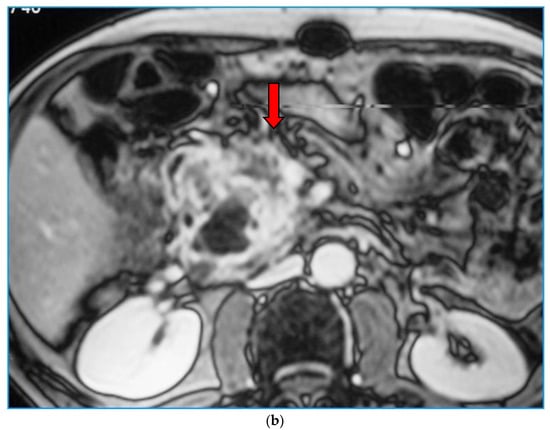

2. Imaging Findings